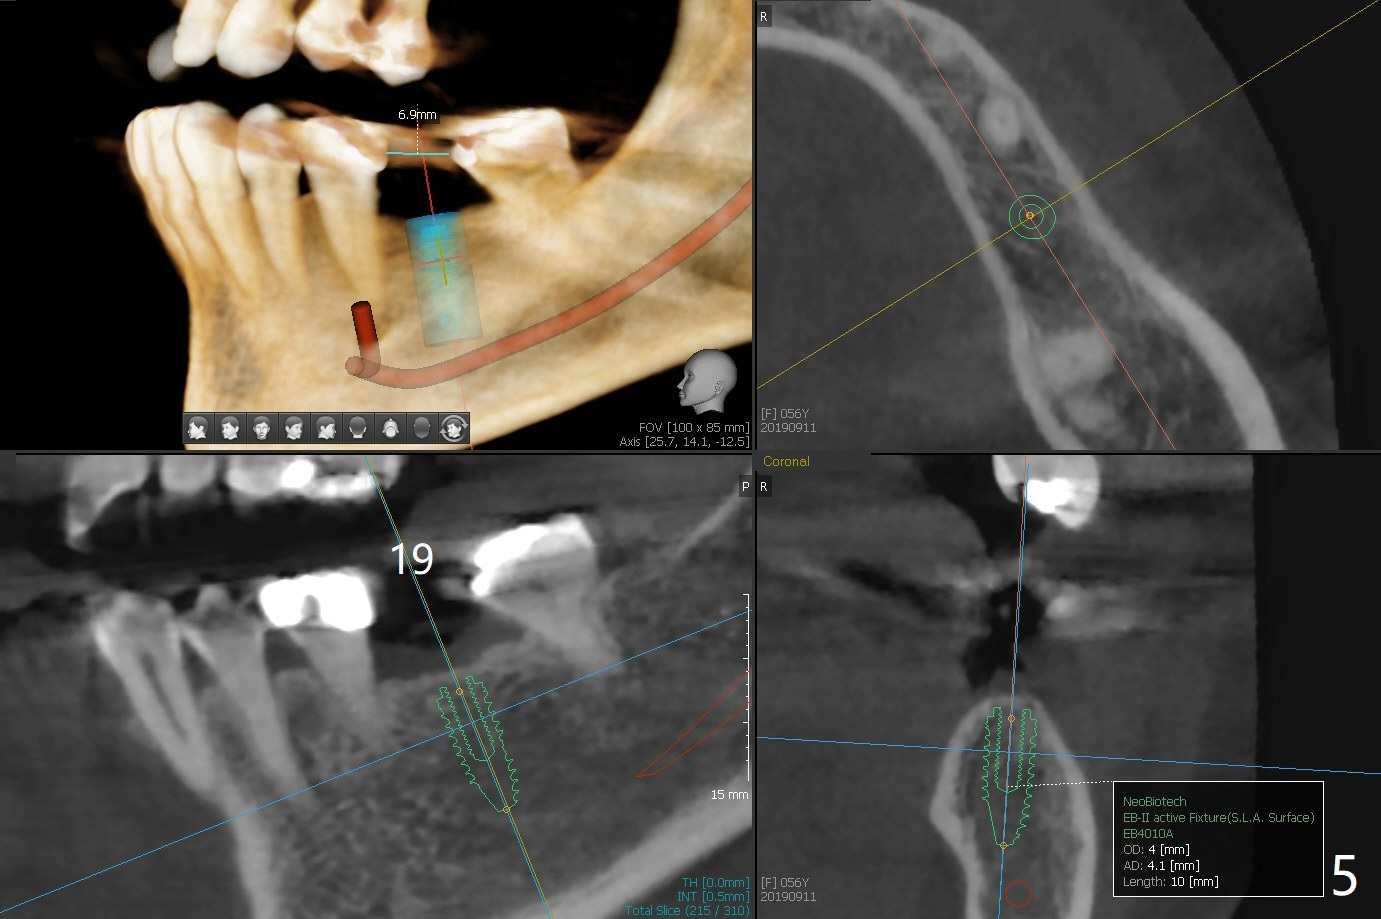

A 56-year-old woman without much posterior support has fractured #7-9 FPD (Fig.1). Since the bone at #7 is thinner buccopalatal than that of #9 (compare Fig.2,3), a shorter implant will be placed at #7 with an angled abutment. External sinus lift is required with PRFx2 before implantation at #14 and 15 (Fig.4). For #19 with the narrow mesiodistal space, a narrow implant is indicated (Fig.5).